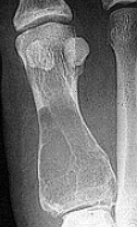

Describe what is occurring at the head of the 3rd met | Freiberg’s infarction (avascular necrosis of the metatarsal head) |